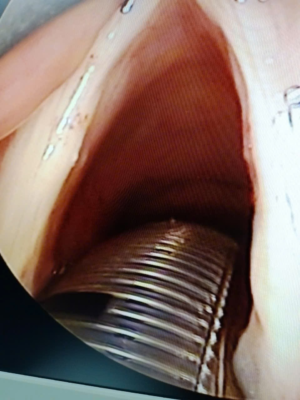

Hình 2: Polyp dây thanh (T)

• Polyp dây thanhcó thể xảy ra ở 1/3 giữa dây thanh và thường một bên. Polyps có xu hướng lớn hơn và lồi hơn so với hạt xơ và thường có một mạch máu chiếm ưu thế nên màu hồng nhạt hoặc hồng đậm hơn Chúng thường là kết quả của một thương tích ngữ âm cấp tính khởi phát. Các bệnh tích polyp khác, thường là hai bên, có thể có nhiều nguyên nhân khác, bao gồm trào ngược dạ dày thực quản, bệnh lý suy giáp chưa được điều trị, phản ứng dị ứng thanh quản mạn tính, hoặc hít chất kích thích mãn tính, như khói công nghiệp hoặc khói thuốc. Tổn thương cấp tính thường gây ra các polyp có cuống, trong khi đó viêm phù nề dây thanh là do kích ứng mãn tính.